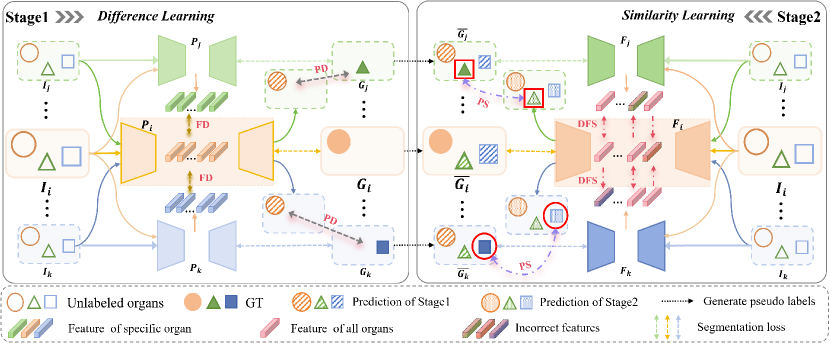

Fig. 3 illustrates the proposed method, which involves two stages. The goal of first stage is to obtain multiple Partial-Organ Segmentation (POS) models, where each POS model, denoted as , acts as a student model to segment different organs. Beyond the supervised learning using its own labels, each also engages in additional difference mutual learning, which includes both Prediction Difference (PD) and Feature Difference (FD). The trained models then generate pseudo labels for other datasets, resulting in combined labeled datasets. The goal of second stage is to train multiple Full-Organ Segmentation (FOS) models using the fully labeled datasets with pseudo labels. Each FOS model, denoted as , acts as a student model to segment all target organs. Similarly, additional Prediction Similarity (PS) and Dynamic Feature Similarity (DFS) mutual learning are introduced during training. Detailed information are as follows.

III-B1 Prediction Difference Learning

As illustrated in Fig. 3, taking dataset as an example, it contains (Input), (GT) and (labeled organ set). The main segmentation loss for is calculated between the network’s predicted results and , as shown in Equation (2). However, when other datasets, such as and , are input into , predictions for organ are generated. Since the labels of organs are mutually exclusive, the predictions for organ should not overlap with the GT in and . Hence, we propose a Prediction Difference (PD) Loss , where a larger loss indicates that the predictions of on other datasets do not overlap with the annotated organs, implying better segmentation performance, as shown in Equation (3).

III-B2 Feature Difference Learning

Simultaneously, to further distinguish the segmentation capabilities of different models, we introduced a Feature Difference (FD) Loss. Specifically, when the image from is input into different student models , , and , the highest-level semantic features extracted by the encoder are , , and . The greater the difference between and and , the larger the difference in features extracted by different models. Therefore, based on and , we incorporate a feature difference mutual learning loss , as shown in Equation (4).

The introduction of difference learning not only enhances the segmentation accuracy of but also enables to perceive the presence of unannotated organs, thereby improving the quality of pseudo labels generated for these organs on other datasets. This method is extended to all training datasets, where PD loss and FD loss is calculated between any two datasets. The specific loss function calculations are as follows:

III-D1 Prediction Similarity Learning

Specifically, taking dataset as an example, the segmentation loss of model is computed from the network output and the labels . The presence of pseudo labels provides additional supervision but can also misguide the model. We note that dataset contains the true labels for organs . When is applied to dataset , it yields prediction results for organs . The loss computed between these results and the true labels of can enhance the performance of in segmenting organs . This loss is termed the Prediction Similarity (PS) Loss, with the main idea being the use of true labels from other datasets for supervision.

III-D2 Dynamic Feature Similarity Learning

In addition to PS loss, we introduce Feature Similarity (FS) Loss similar to the first stage. However, unlike the first stage, each in this stage can segment all organs comprehensively. The highest-level semantic features extracted by each student model includes features for all organs. Directly computing mutual learning loss could lead to inaccuracies, as features are extracted from models trained on pseudo labels. Given that and have different segmentation capabilities for different organs, we dynamically transfer the correct features between the two student models in the latent space to benefit each other. However, determining the direction of knowledge transfer during training is a challenging problem. Inspired by the mutual learning between CNN and Transformer [16], we propose managing the direction of knowledge transfer by combining prediction results with true labels, as follows:

Given the features extracted by from and extracted by from , we first compute the cosine similarity . Then, we quantify the reliability of the knowledge between the two students using the cross-entropy loss between prediction and true labels. Specifically, we use to represent the direction of feature transfer. We calculate the prediction results of on and of on , respectively, and then compute the cross-entropy loss with true labels to obtain and . If is larger than , it indicates that is more accurate than , so , meaning the feature is transferred from to . Otherwise, . Through this approach, and can exchange reliable knowledge, enabling the correct transfer of features, which is called Dynamic Feature Similarity (DFS) Loss.